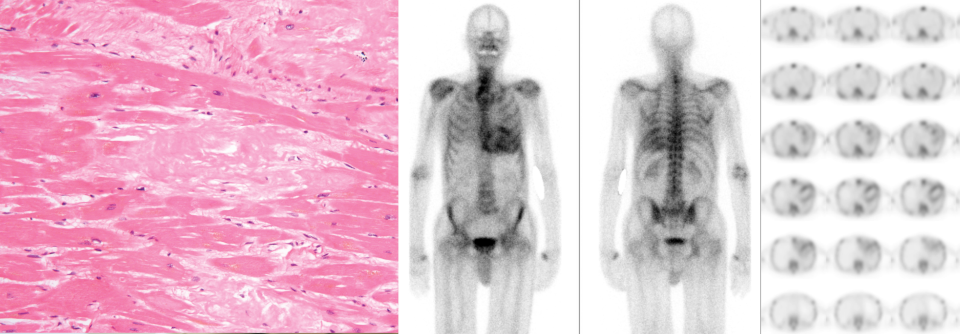

Algorithmen in der Therapie Ist es eine kardiale Amyloidose?

Um Patienten mit kardialer Amy­loidose rasch und zielgerichtet zu therapieren, muss die Erkrankung schneller entdeckt werden. Neue Ansätze sehen­ vor, die notwendigen Untersuchungen in einem Rutsch durchzuführen. Das kann auch abseits spezialisierter Zentren gelingen.